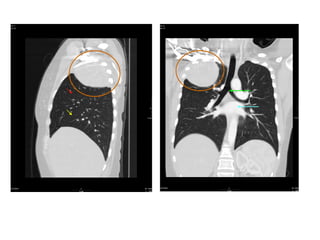

VỠ LOÉT ĐỘNG MẠCH CHỦ NGỰC

-> MÁU XOANG NGỰC (T)